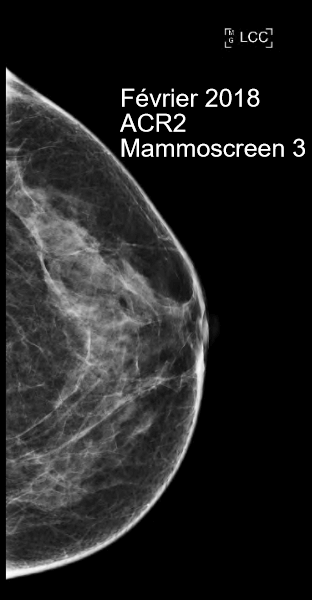

En février 2018, cette patiente a réalisé un examen de dépistage classé ACR2, le MammoScreen Score™ 3 sans élément suspect en particulier à gauche.